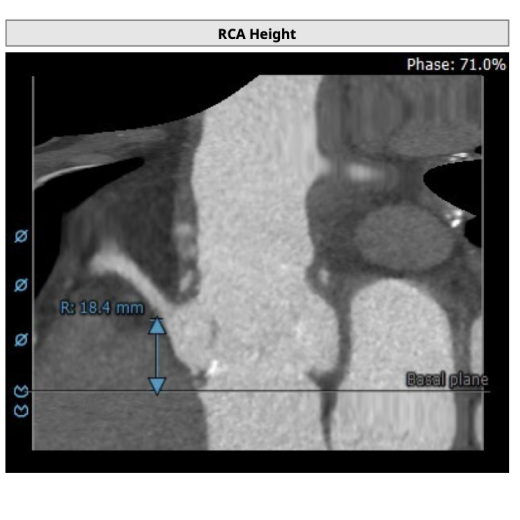

左冠高度:19.4mm,右冠高度:18.4mm